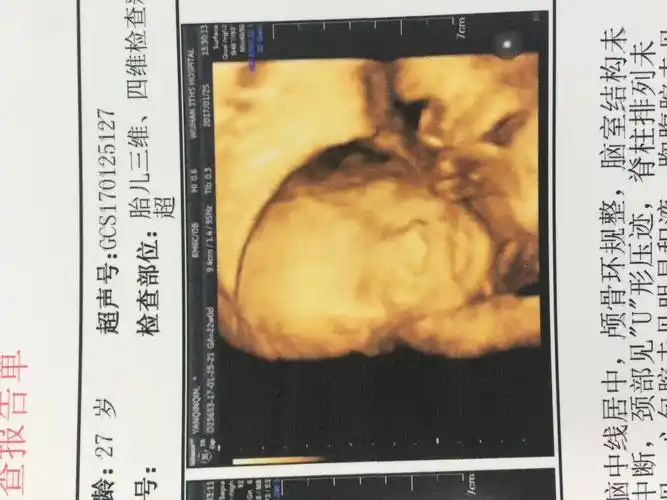

六个月胎儿图

胎儿六个月频繁活动

好孕帮!六个月四维彩超男孩图"兢兢业业"-第1张图片-吉泽网